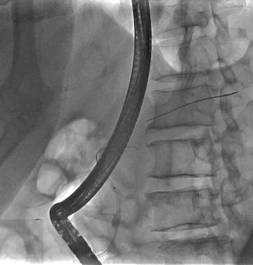

诊疗过程:患者高龄,一般情况差,手术风险高,患者及家属选择ERCP胆道支架植入及光动力治疗(不开刀、经自然腔道的微创手术,患者痛苦小)。ERCP术中因胆总管下段闭塞导丝不能进入胆总管,但是胰管插管成功,予以放置胰管支架(可改善胰管引流不畅,减轻胰管高压,改善消化功能);二期予以经皮经肝胆管穿刺(PTC)成功放置胆道支架(同样为微创,只需皮肤切开3mm的小口);待患者黄疸消退、全身情况改善后予以内镜下胆道肿瘤光动力消融术。术后多次复查腹部CT均提示胆总管下段肿瘤呈坏死的低密度灶,无复发征象。

内镜逆行插管仅进入胰管,胆总管下段闭塞,插管不成功;内镜下放置胰管支架。 | |

经皮经肝胆道穿刺顺行疏通胆总管 |